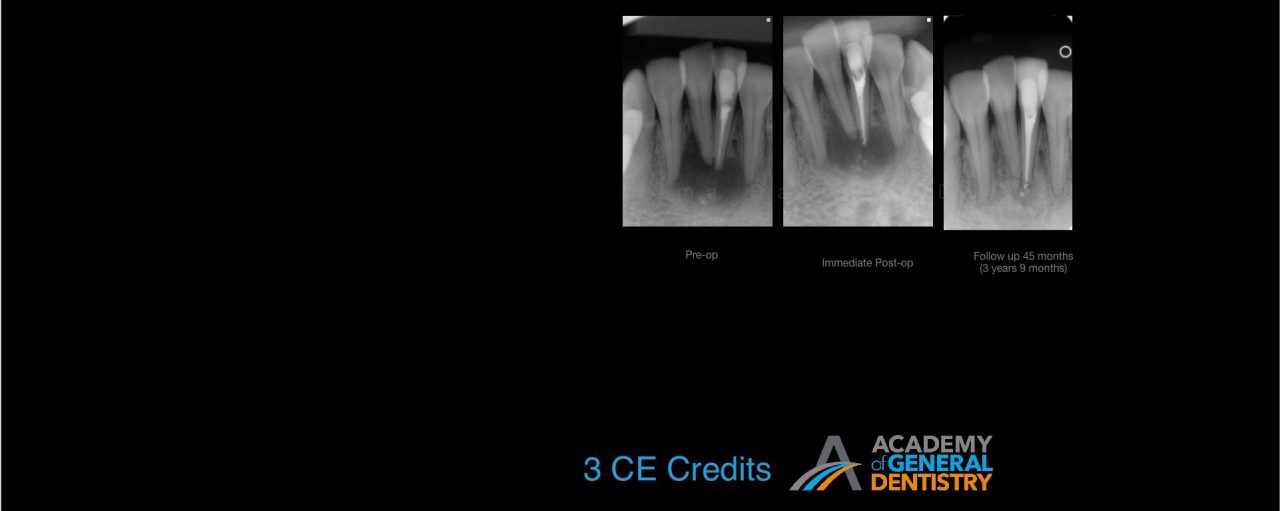

According to literature, the survival rate of endodontically treated teeth is close to 98%. How do we update our understanding of endodontics so that we can care for our patients and close in on the 98% published survival rate? The most common reason for a failed root canal treatment is inadequate treatment. However, there are some cases in which a root canal treatment is carried out in accordance with the highest standards, and yet still results in failure. In most such cases, the endodontic failure results from persistent intra-radicular infection. In other cases, extra-radicular infections and intrinsic or extrinsic non-microbial factors might be implicated in the failure.

The purpose of this lecture is to discuss the etiological factors of failed root canal treatments using a series of clinical cases. It will aid clinicians in choosing between surgical and non-surgical management of a failed root canal in an evidence-based manner. Indications for the non-surgical vs. surgical retreatment of failed endodontic cases are discussed in order to maximize the success of an endodontic retreatment.